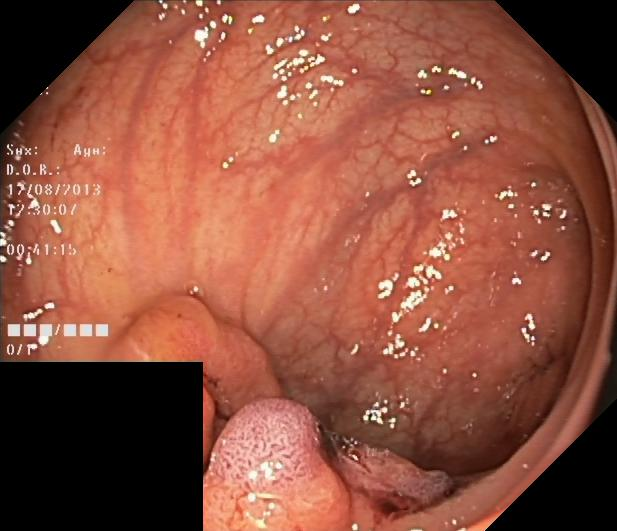

Figure 3: Qualitative results on all three segmentation tasks. The figure shows an example image, ground truth (GT) and predicted (PRED) segmentation mask for the skin lesion segmentation task (row 1), the polyp segmentation task (row 2) and retinal vessel segmentation task (row 3).

We have provided the additional qualitative results of our method for all three segmentation tasks. Fig. 5, shows the qualitative results of skin lesion segmentation, while Fig. 6 and Fig. 7, illustrate the visualization of retinal vessel and polyp segmentation tasks respectively.

Refer to caption

IMAGE

GROUND TRUTH

PREDICTED MASK

Figure 7: Visualizations of polyp segmentation